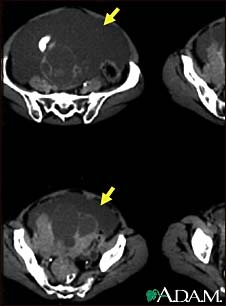

Ascites with ovarian cancer, CT scan

This CT scan of the lower abdomen shows a massive amount of free abdominal fluid (ascites) in a patient with ovarian cancer.